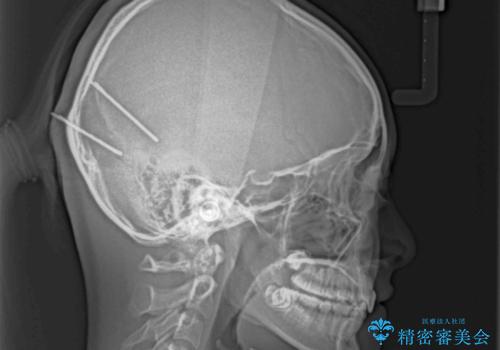

奥歯の咬み合わせを見ると、上顎が下顎に対して相対的に前方にありました。

咬み合わせも深くなっていたため、上顎臼歯を後方に移動させつつ、下顎の小臼歯を直立させ、奥歯の咬み合わせを改善する必要があります。

インビザライン単体で対応することも検討できますが、達成する可能性が低いため、カリエールディスタライザーという補助装置を併用して、より確実性を上げることとしました。

奥歯の咬み合わせと深い咬み合わせを改善した後、隙間などをインビザラインで整えることとしました。